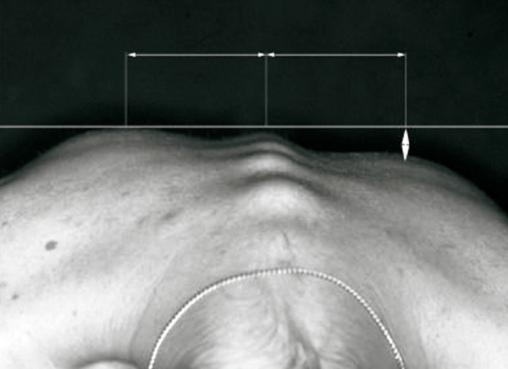

Cette anomalie des courbures dorsales est le signe clinique pathognomonique d'une scoliose. La gibbosité se démasque lorsque le patient se penche en avant, les genoux restant en rectitude.